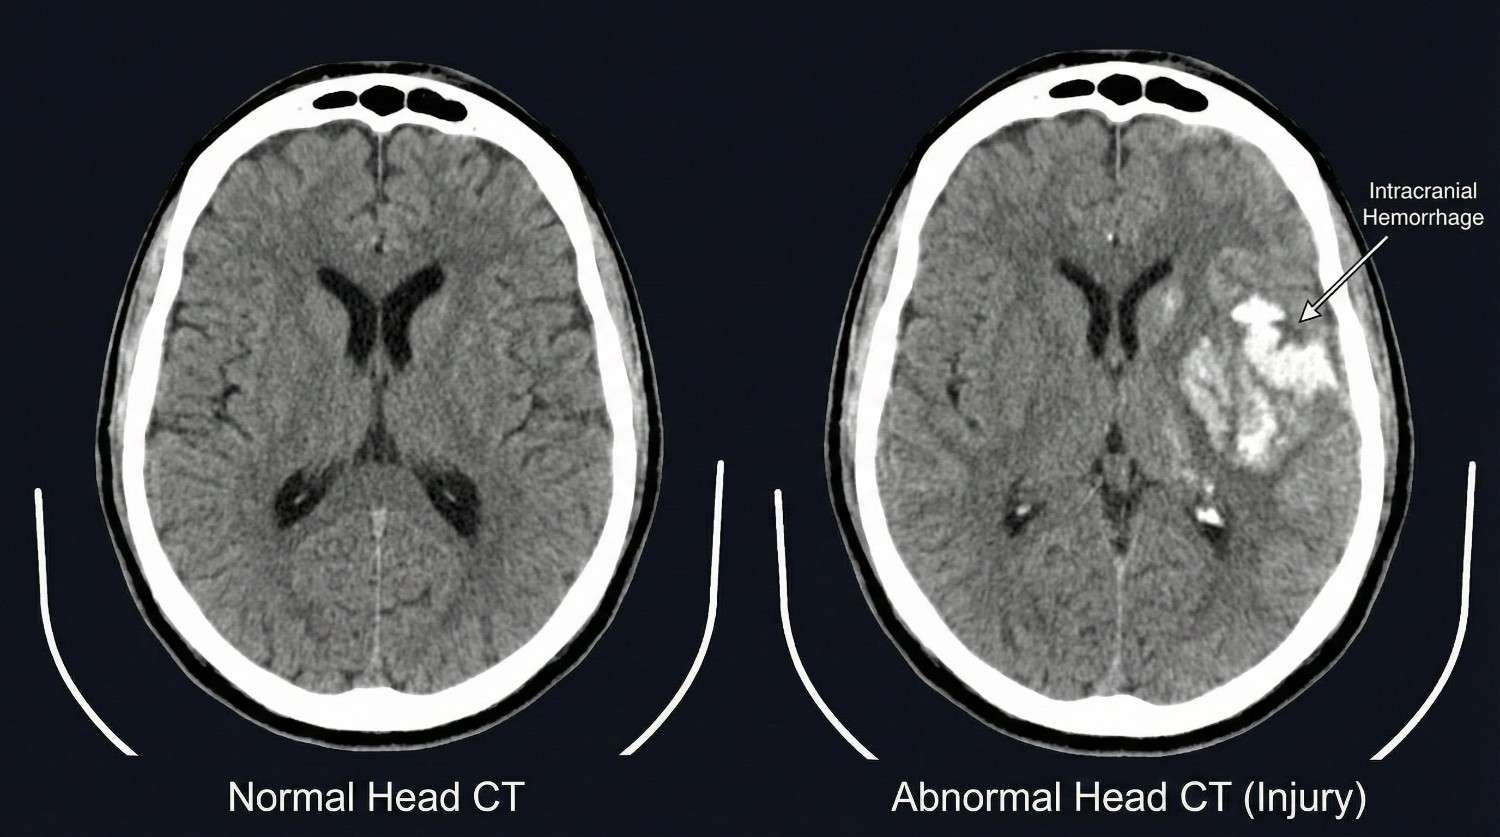

Vascular emergency signs include severe headache with sudden onset reaching maximum intensity within seconds ("thunderclap headache" suggests vertebral artery dissection or subarachnoid hemorrhage), headache with vision changes such as double vision, visual field cuts, or transient blindness (posterior circulation stroke from vertebral artery injury), dizziness with dysphagia (difficulty swallowing), dysarthria (slurred speech), or facial numbness (brainstem stroke), and Horner's syndrome (ptosis, miosis, anhidrosis indicating sympathetic chain disruption from carotid or vertebral artery dissection).

When any of these red flag symptoms develop, we instruct patients to proceed immediately to the emergency department, preferably one with neurosurgery capabilities. Memorial Hermann Southeast Hospital, Houston Methodist Baytown Hospital, and Clear Lake Regional Medical Center all have neurosurgical coverage and advanced imaging available 24/7. After emergency stabilization and treatment, patients return to our care for ongoing management coordinated with the emergency intervention.